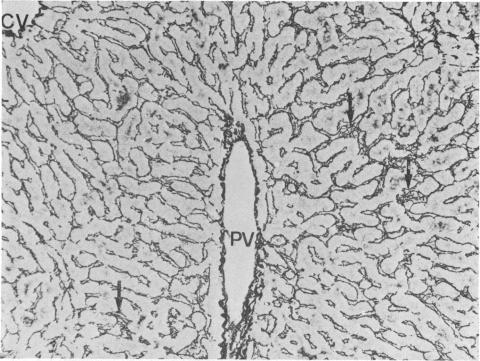

We report the cases of two renal transplant recipients suffering from idopathic portal hypertension, a condition characterised by increased portal venous pressure in the absence of both histological lesion of the liver and obstruction of the portal vein. In these two patients, perisnusoidal fibrosis, invisible by light microscopy, was demonstrated by electron microscopy; it is suggested that partial obstruction of hepatic sinusoids by perisinusoidal fibrosis could be the mechanism for increased portal venous pressure in all the patients with idiopathic portal hypertension. In these two patients, who received 6-mercaptopurine and azathioprine, perisinusoidal fibrosis might be the consequence of prolonged administration of these drugs.

我们报告了两例患有特发性门静脉高压症的肾移植受者病例,该病症的特征是在没有肝脏组织学病变和门静脉阻塞的情况下门静脉压力升高。在这两名患者中,光镜下不可见的窦周纤维化通过电子显微镜得以证实;有人提出,窦周纤维化导致的肝血窦部分阻塞可能是所有特发性门静脉高压症患者门静脉压力升高的机制。在这两名接受6-巯基嘌呤和硫唑嘌呤治疗的患者中,窦周纤维化可能是长期使用这些药物的结果。